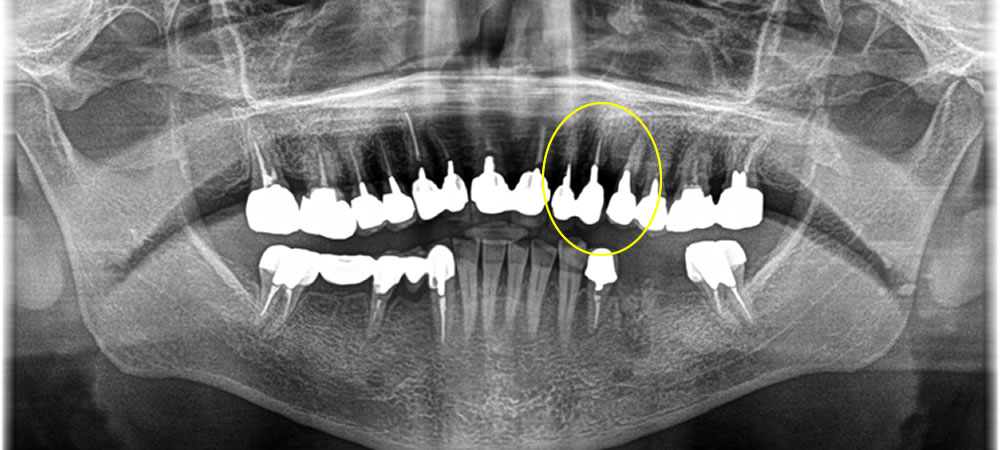

保存不可能な歯を抜歯後にインプラントで治療した症例

こちらは歯がグラグラして他院にて保存不可と診断された患者さまです。インプラント専門の当院にてインプラント治療を行いたいとの事でお越しいただきました。

前歯なので、審美的要素を重要視し歯茎が下がる事を極力抑えるために抜歯即時でインプラントを埋入し、骨を作る処置も同時に行いました。

抜いた時には唇側の骨が欠損してしまっていましたが、無事歯茎が下がる事を最小限に抑え上部の歯を作成する事ができました。

年齢60代

性別男性

費用CT検査 0円

インプラント治療 (上部ジルコニア含め)

451,000円×2

429,000円

骨造成(ソケットプリザベーション) 88,000円×3

治療期間5ヵ月

治療回数5回